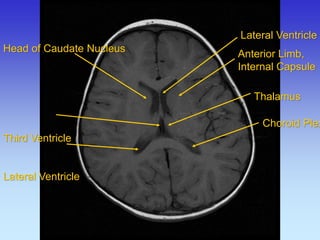

Head of Caudate Nucleus Posterior Limb, Internal Capsule

Genu,

Corpus Callosum

Anterior Limb,

Internal Capsule

Thalamus

Lateral Ventricle

Choroid Plexus

Anterior Limb, Internal Capsule

Head of Caudate Nucleus Third Ventricle Lateral Ventricle